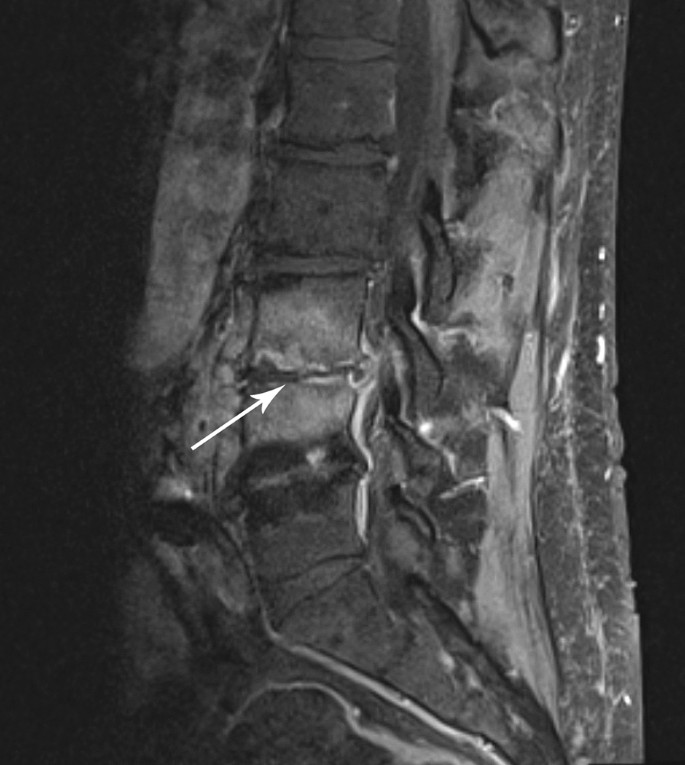

The patient had been well until ~ 6 weeks prior when isolated lower back pain developed. At that time, an outpatient non-contrast-enhanced magnetic resonance imaging (MRI) of the lumbar spine demonstrated significant edema within the vertebral bodies adjacent to the L4–L5 intervertebral disc space. Given his absence of systemic symptoms, short-term follow-up was advised. Two weeks later, a repeat contrast-enhanced MRI of the lumbar spine demonstrated progressive T2 hyperintensity at the L4–L5 intervertebral disc space and adjacent endplates with near complete involvement of the L3 and L4 vertebral bodies, highly suggestive of vertebral osteomyelitis and discitis (Fig. 1a). In addition, there was a 6 mm thick anterior epidural thickening and enhancement suggestive of epidural phlegmon that extended to L3 superiorly, S1 inferiorly, and the posterior wall of the known abdominal aortic aneurysm anteriorly (Fig. 1b). He was admitted for further workup and management.